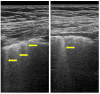

Systemic sclerosis (SSc) is a complex autoimmune disease characterized by significant fibrosis of the skin and internal organs, with the main involvement of the lungs, kidneys, heart, esophagus, and intestines. SSc is also characterized by macro- and microvascular damage with reduced peripheral blood perfusion. Several studies have reported more than 240 pathways and numerous dysregulation proteins, giving insight into how the field of biomarkers in SSc is still extremely complex and evolving. Antinuclear antibodies (ANA) are present in more than 90% of SSc patients, and anti-centromere and anti-topoisomerase I antibodies are considered classic biomarkers with precise clinical features. Recent studies have reported that trans-forming growth factor β (TGF-β) plays a central role in the fibrotic process. In addition, interferon regulatory factor 5 (IRF5), interleukin receptor-associated kinase-1 (IRAK-1), connective tissue growth factor (CTGF), transducer and activator of transcription signal 4 (STAT4), pyrin-containing domain 1 (NLRP1), as well as genetic factors, including DRB1 alleles, are implicated in SSc damage. Several interleukins (e.g., IL-1, IL-6, IL-10, IL-17, IL-22, and IL-35) and chemokines (e.g., CCL 2, 5, 23, and CXC 9, 10, 16) are elevated in SSc. While adiponectin and maresin 1 are reduced in patients with SSc, biomarkers are important in research but will be increasingly so in the diagnosis and therapeutic approach to SSc. This review aims to present and highlight the various biomarker molecules, pathways, and receptors involved in the pathology of SSc.